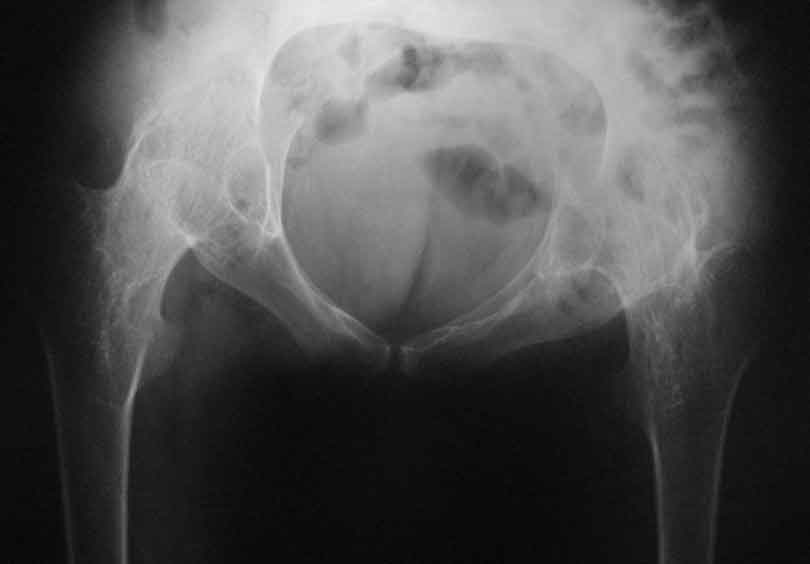

Уважаемые коллеги, в отделении находится пациент 28 лет, страдающий ревматоидным артритом с детства. В настоящее время основной проблемой для него являются тазобедренные суставы - костный анкилоз в положении сгибания около 80 град.

Привет Максим. На двух анкилозах передвигаться крайне плохо. Раз ходит - то небольшая часть мышц окружности т.б сустава есть, это видно и на фото. Пошел бы по пути разанкилозирования и бесцементник с каждой стороны поочередно.

Максим, мы протезировали 2х подобных больных. В случае с семилетним анкилозом на фоне болезни Бехтерева функция сустава осталась значительно ограниченой, но больная вполне сносно передвигалась. В другом случае на фоне ревматоидного артрита 4х летний анкизоз у молодого парня получен очень хороший функциональный результат. В обоих случаях использовали бесцементные протезы.

Следует учесть тот факт, что нечто принимаемое за хорошую кость во впадине по рентгенограмме, может оказаться очень неприятной пустотой с порозными балочками. При выборе размеров чашки это следует учесть, а в целом результаты не разочаровывают.

Я бы делал все в один этап, т.к. ситуация по контрактуре не критична. Но при любых анкилозах есть трудности - прежде всего - направление остеотомии шейки бедра. При использовании переднего доступа очень легко ошибиться и "снести" заднюю стенку ВВ, лучше несколько раз перепроверить направление. Обязательно нужно сделать двойную остеотомию для создания необходимого про-ва для обработки ВВ. Необходимо очень не спеша определиться с маркерами ВВ, т.к. обрабатывать впадину Вы будете прямо по головке и иногда бывает сложно понять где находишься. В случае затруднения лучше сделать Р-контроль. В любом случае Вам надо сделать расширенный релиз для достижения хорошей интраоперационной амплитуды движений. И последнее - многие пациенты остаются неудовлетворенными р-ми операции из-за чувства нестабильности, "провала" в суставе, выраженной хромоты. Это связано с длительным бездействием мышц. Это не значит, что не надо делать операции, просто это надо иметь ввиду и объяснять пациентам.